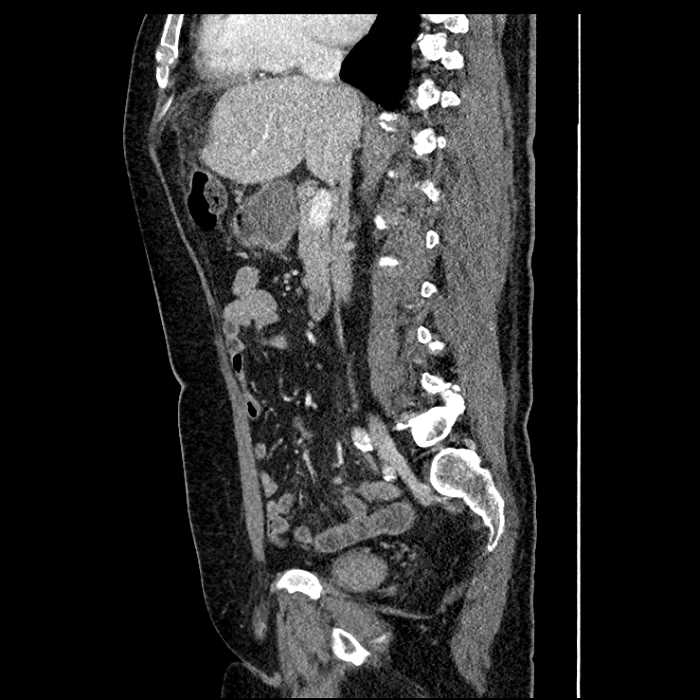

Acute sigmoid diverticulitis complicated by a small contained perforation and a large abscess in the right hepatic lobe. Additional small subcapsular abscesses along the anterior margin of the left hepatic lobe.

Additionally, loss of the normal fat plane between the peridiverticular collection and adjacent thickened loops of small bowel raises the potential for an enterocolonic fistula.

• The classic CT imaging appearance is a double target sign with internal low density surrounded by an internal enhancing rim (capsule) and a low density external rim (edema)

Hepatic abscess showing the double target sign with low density internally surrounded by a thin inner enhancing rim (red arrow) and ill-defined outer low density rim (yellow arrow). Blue arrow indicates an internal septation. Red arrows: additional smaller subcapsular abscesses. Red arrow: focal contained perforation associated with diverticulitis.